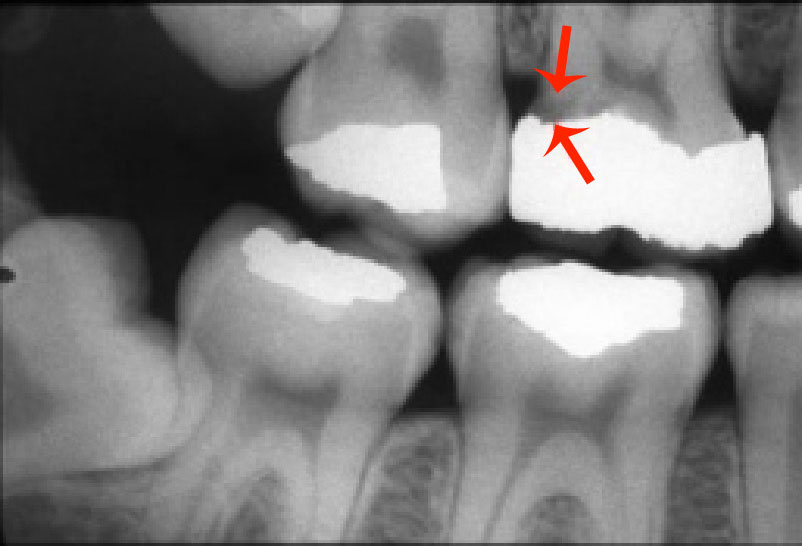

Secondary or Recurrent Caries (Figure 5). Includes caries seen adjacent to or beneath an existing restoration.

Figure 5. Secondary or recurrent caries.

Figure 5